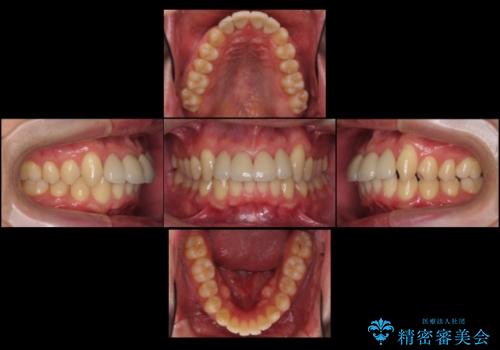

- 前歯のすき間を気にして来院。

矯正治療か、セラミックで最短で治すかの選択肢を提示し、セラミックで治すことにしました。

利点は、早く終わる上に、保定の必要がないため負担が少ないことが挙げられます。

ただし、セラミックは欠ける特性があるため、夜はナイトガードを使用していただくことにしました。

全て神経は取らずに、削りました。

長年コンプレックスだったすき間が閉じたとのことで、喜んでいただきました。